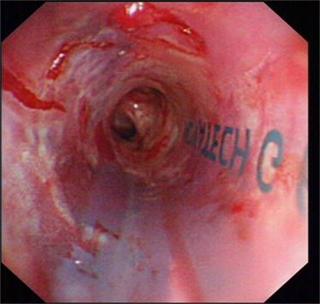

近日我科为一食道癌晚期、食道气道瘘的患者成功放置硅酮支架,患者在禁食1月后终于再次尝到了香甜的米饭,激动万分。该患者1年前在外院确诊为食道癌晚期,一直在我院放化疗科进行化疗及放疗,后患者逐渐出现进食后呛咳,复查胸部CT提示食道癌气道广泛侵袭,存在气道食道瘘可能。患者为避免进食后呛咳,已留置鼻饲,禁食1月。经我科俞万钧副院长会诊,决定为患者进行气道硅酮支架置入堵瘘口,让患者恢复进食。硅酮支架堵瘘术目前国际上开展不多,国内更是寥寥无几,手术难度大,成功率低。手术当日,俞万钧副院长亲自主刀,首先对气道浸润的肿瘤进行消融处理,后成功放置Y型硅酮支架,封堵瘘口。术后次日,患者就能进食流质,再次体会到进食的快乐。利用Y型气道硅酮支架封堵瘘口,全省目前未见报道,全国只有天坛医院,厦门二院等几家医院实施过,这一手术标志着我院硬镜,硅酮支架放置技术达到全国领先水平。(徐涛)

图片4 硅酮支架帮助重建气道